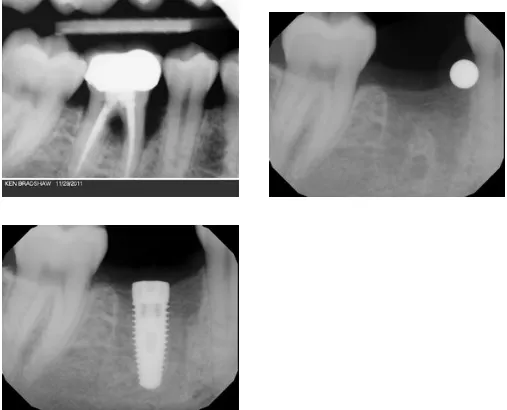

Dental Implant and Ridge Augmentation

Ridge modification is an effective procedure for treating deformities in the upper and lower jaws.  These deformities can occur as a result of periodontal disease, trauma, injury, wearing dentures, or developmental problems.  Such defects can leave insufficient bone for the placement of dental implants and an additional unattractive indentation in the jaw line adjacent to the missing teeth.

During the ridge modification procedure, the gum is lifted away from the ridge to fully expose the defect in the bone.  The bony defect can be filled with bone graft material which can help regenerate lost bone, or a bone substitute.  Finally, the incision is closed and several months of healing will be required.  Depending on the case and type of implant and procedure, a dental implant may be placed during the ridge modification procedure or when healing is complete; much depends on the precise condition of the bone.  Ridge modification improves the cosmetic appearance, functionality of the mouth, and the chance of enjoying dental implants for many years.

Before & After